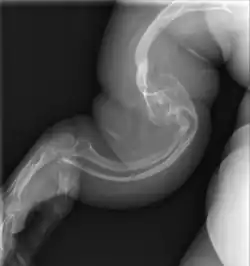

Collagen is fatally defective at its C-terminus.[5]: 1512 Most cases result in death shortly after birth, or within the first year of life, due to respiratory failure. Another common cause of death is intracranial bleeds from skull fractures present at, or sustained during or shortly after, birth.[5]: 1511 In many cases, the newborn already has multiple broken bones at the time of birth. Type II infants also exhibit severe respiratory problems and have severely deformed bones. Sixty percent of infants die less than 24 hours after being born, and survival after the first year is extremely unlikely and normally requires mechanical ventilation.[57] In the rare cases of infants who survive their first year of life, severe developmental and motor delays are seen; neither of two infants studied in 2019, both aged around two years, had achieved head control, and both required a ventilator to breathe.[58]

Type II is also known as the "lethal perinatal" form of OI,[59] and is not compatible with survival into adulthood.[57] Due to similarly severely deformed bones, sometimes infants with severe type III are wrongly initially classified as type II; once long-term survival is shown, they are considered as having type III instead.[5]: 1511 [60]

OI type III causes osteopenic bones that fracture very easily, sometimes even in utero, often leading to hundreds of fractures during a lifetime;[24] early scoliosis that progresses until puberty; dwarfism (a final adult height frequently less than 4 feet or 120 centimetres); loose joints; and possible respiratory problems due to low rib cage volume causing low lung volumes.[5]: 1512

An OI diagnosis can be confirmed through DNA or collagen protein analysis, but in many cases, the occurrence of bone fractures with little trauma and the presence of other clinical features such as blue sclerae are sufficient for a diagnosis. A skin biopsy can be performed to determine the structure and quantity of type I collagen. While DNA testing can confirm the diagnosis, it cannot absolutely exclude it because not all mutations causing OI are yet known and/or tested for.[83]: 491–492 OI type II is often diagnosed by ultrasound during pregnancy, where already multiple fractures and other characteristic features may be visible. Relative to control, OI cortical bone shows increased porosity, canal diameter, and connectivity in micro-computed tomography.[98] OI can also be detected before birth by using an in vitro genetic testing technique such as amniocentresis.[99]